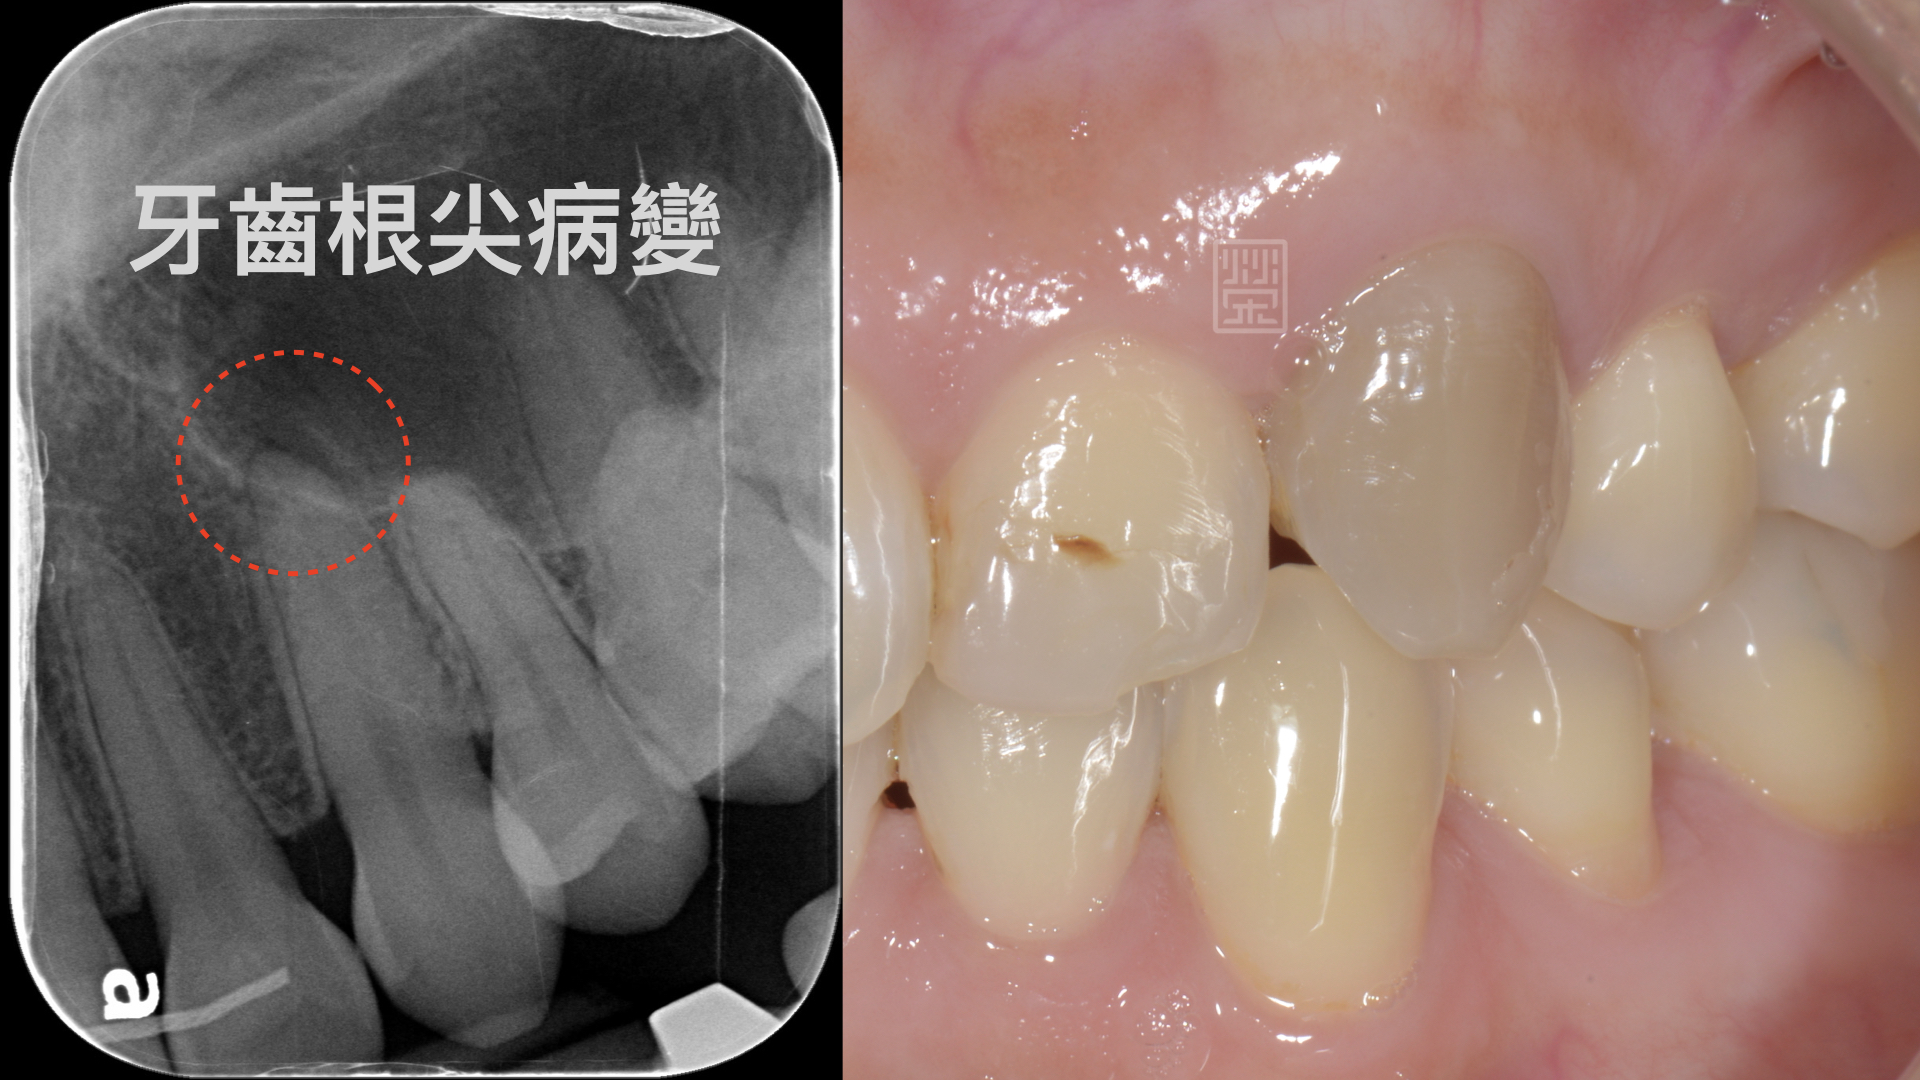

雖然牙齒顏色隨著牙釉質耗損,慢慢變暗,但是突然變暗這一定是有其他的原因,口內檢查,變色的犬齒並沒有蛀牙;但在X光片檢視下,發現牙齒根尖有黑色陰影,這表示牙齒神經已經病變壞死了,但這是為什麼呢?為什麼沒有蛀牙,牙齒神經也會受傷嗎?

X光片中發現根尖陰影